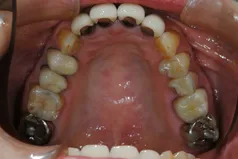

[症例2]

治療前は臼歯部は保険の冠のため金属色が目立ちます。上顎の前歯はセラミックですが、古いタイプの治療法ため裏側に金属が露出しています。

矯正治療後に部分被せも含めて全てセラミックで治療しました。

右下6番は歯を真ん中で分割して2本の冠が入っていましたが、抜歯してインプラントが入っています。

上下顎とも金属色の見えない美しい歯並びになりました。

- 治療期間:約1年

- 治療費:240万円

- 治療回数:26回